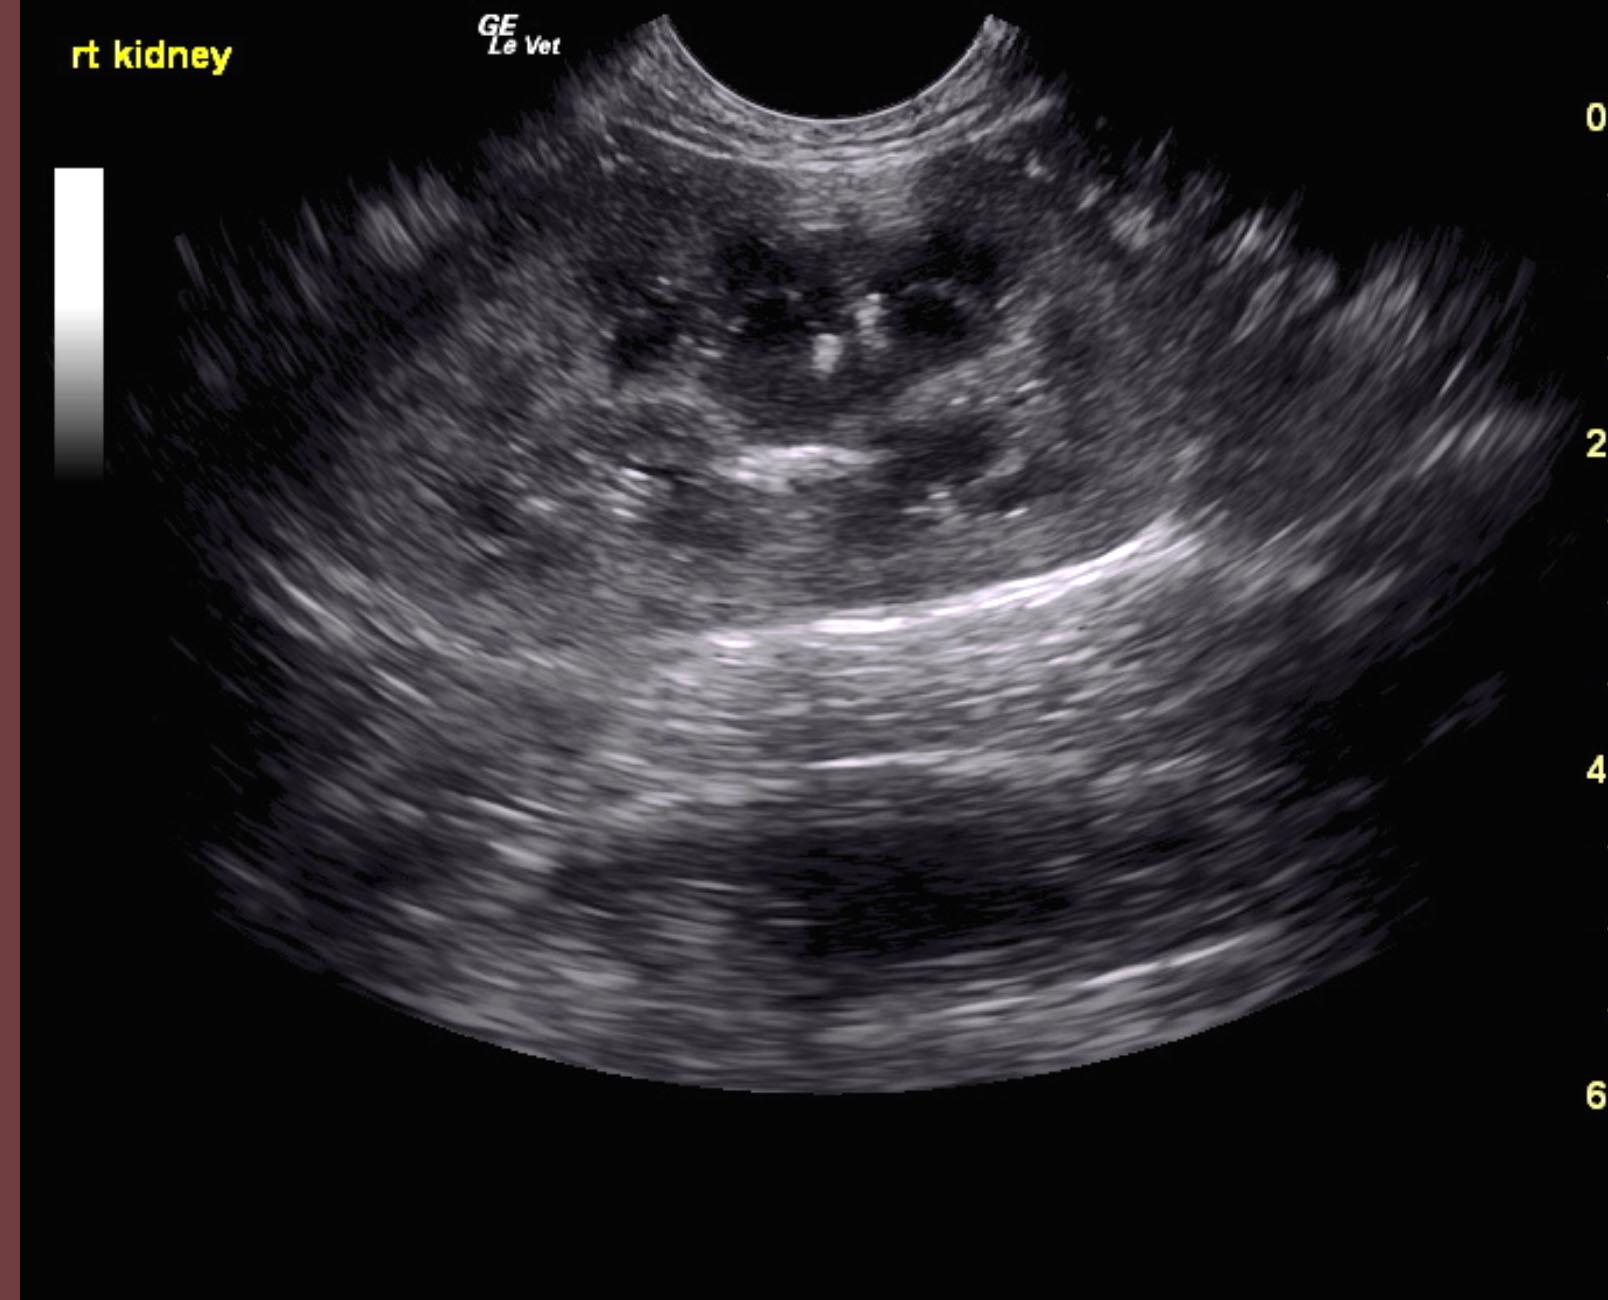

The kidneys were swollen in this patient. The left kidney measured 4.83 cm with medullary rim sign and slight mineralization. The right kidney measured 4.93 cm with dystrophic mineralization and swollen contour.